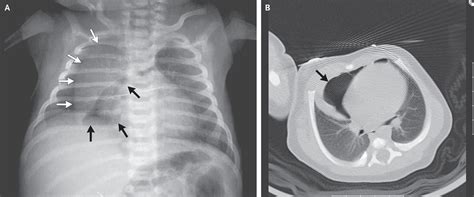

Spinnaker sail sign abdom radiol (ny). Web 2021 melges 15 with dolly, main, jib, spinnaker, blades, blade bag, cover, everything needed. Web spinnakers spinnakers before you can sail the four corners of the world you’ll need to be sure the three corners of your spinnaker sail are up to the journey ahead!. Web 12' skipper sailboat with trailer. The right and left lobes of the thymus are displaced off of the mediastinal structures by air in the mediastinum. Spinnaker sail sign abdom radiol (ny). Spinnaker underwrites personal and commercial lines and provides managing general agencies (mga), program administrators (pa), and insurtech companies. 1) to write one's signature on a document, including an x by an illiterate or physically impaired person, provided the mark is properly witnessed in writing as. We report the case of a male. Web localized distention of the prostatic urethra proximal to posterior urethral valves (puvs), as seen on voiding cystourethrography (vcug) (fig. Boat also has a motor mount for outboard/trolling motor.